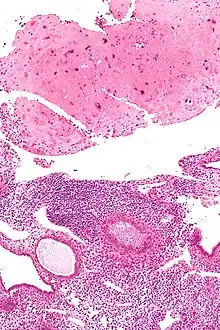

Micrograph of a placental site nodule (top of image). H&E stain.

Typically, they consist of pink (hyaline) material using the standard stain and contain few cells. Bizarre multinucleated cells may be present; however, there is no mitotic activity. The differential diagnosis includes (cervical) squamous cell carcinoma, gestational trophoblastic disease, and exaggerated placental site.